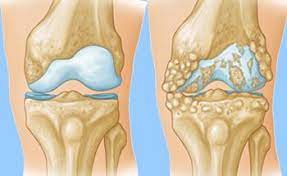

4.अर्थराइटिस

अर्थराइटिसब्लड फ्लो धीमा होता है |

ठंडा मौसम कटिया के दर्द को बढ़ा सकता है तेज ठंड से ब्लड फ्लो धीमा हो सकता है दर्द के प्रति शेयर की संवेदन बढ़ जाती है अक्सर जैसे-जैसे तापमान गिरता है वायुमंडल में हवा के दबाव बैरोमीटर का दबाव की मात्रा भी बदल जाती है इसमें से कुछ लोगों को जोड़ों में दर्द बढ़ता है |

उपाय – क्या करें पर्याप्त पानी और तरल पदार्थ पिए

डिहाइड्रेशन दर्द के प्रति अधिक समिति सेल बनता है वहीं जब पर्याप्त पानी पीते हैं तो टॉक्सिंस को बाहर निकलने में मदद मिलती है इसके अलावा यह जोड़ों में घर्षण को काम करता है |